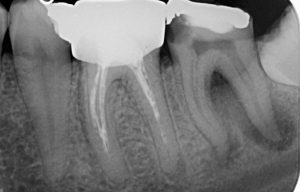

Лечение на гранулом

Случай на случайно открит периодонтит на долен седми зъб. Пациентът дойде при нас, защото “му задържа храна” между два зъба. Рентгенологичната находка ни сблъска с много по-сериозен проблем, лечението на който отне повече от 2 месеца. Седмият зъб бе с диагноза хроничен апикален периодонтит, а грануломът бе обхванал целият зъб, включително и фуркацията на зъба. При шестия зъб положението не беше толкова драматично, но също се наложи да се прелекува, поради същата диагноза като съседния.

Днес, две години след лечението, няма и помен от проблеми и пациентът очаква поставянето на брекетите на долната си челюст.